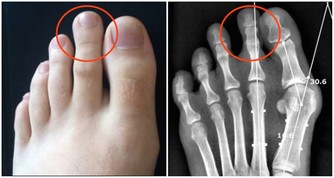

1. 骨骼:

35 歲後骨密度會自然流失,80 歲時身高會降低5 公分。